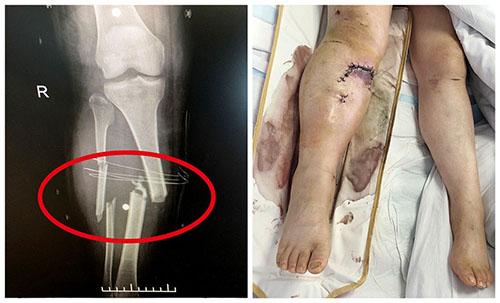

▲遭遇車禍的患者全身多處嚴(yán)重骨折

穩(wěn)住后,如何選擇較優(yōu)治療方案成為頭等大事。潘仁龍邀請(qǐng)滬上知名三甲醫(yī)院專家前來會(huì)診后,形成了兩套治療方案——一是“先促醒,后接骨”,二是“先接骨,再促醒”。當(dāng)時(shí),外院專家傾向于第一種方案,認(rèn)為先確認(rèn)患者有機(jī)會(huì)從昏迷中蘇醒,而非成為植物人,其他治療才有意義。而潘仁龍則認(rèn)為,患者骨折情況嚴(yán)重,且左側(cè)肩胛粉碎性骨折出現(xiàn)大出血,不進(jìn)行骨科手術(shù)治療恐危及生命。最終,大家達(dá)成共識(shí),采用了第二套治療方案。